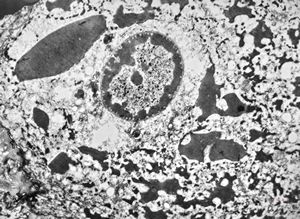

F, 57y. | mycosis fungoides … cerebriform nucleus of Sézary cell